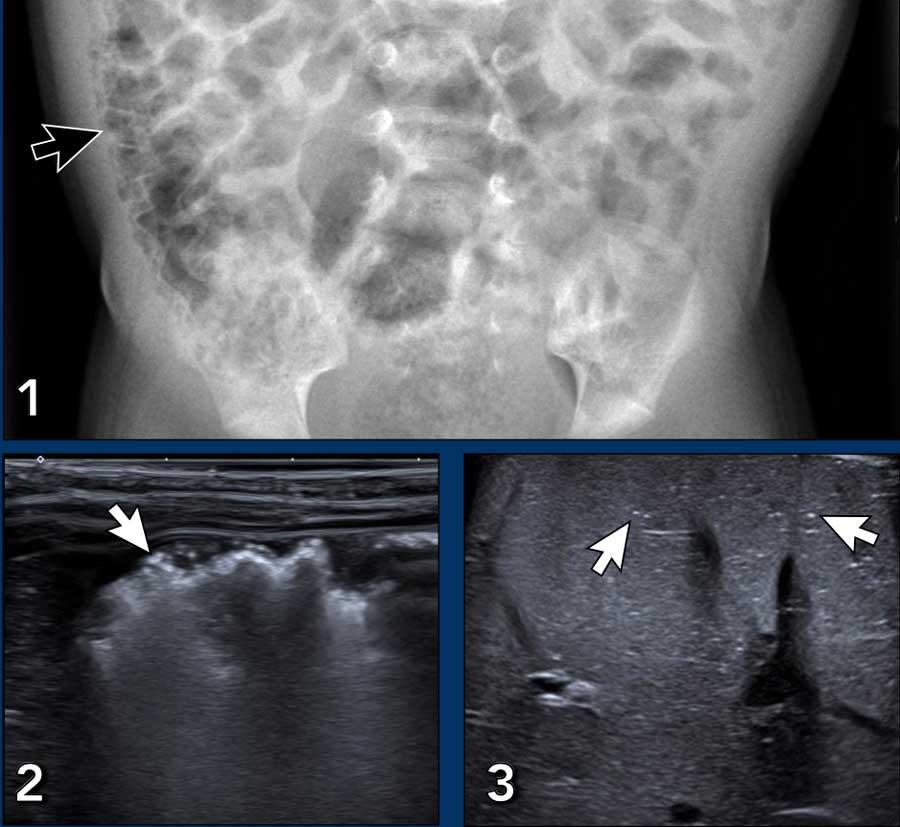

Hình ảnh

Bé trai 4 tháng tuổi đã phẫu thuật tim bẩm sinh phức tạp, hiện có phân lẫn máu.

X-quang bụng cho thấy khí trong thành ruột (pneumatosis) (mũi tên).

Dấu hiệu này cũng được thấy trên siêu âm ở đoạn ruột bên trái, trong khi đoạn ruột lành bên phải cho thấy các phản âm hơi bình thường.